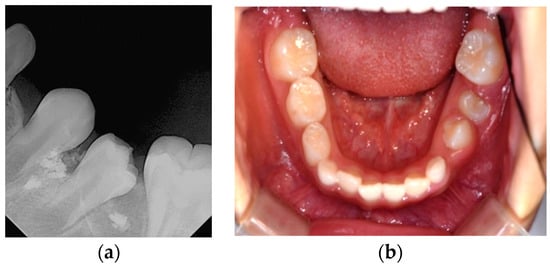

Six months after treatment, the cyst size was significantly reduced, and the premolars had erupted (Figure 5). Thirty months after treatment, the extruded canal filling material remained around the roots of the erupted left mandibular premolars (Figure 6). The patient showed no clinical symptoms.

Figure 5.

Six months after marsupialization: (a) periapical radiograph; (b) intraoral photo. Left mandibular premolars have erupted and extruded canal filling materials still exist.

Figure 6.

Thirty months after marsupialization. Panoramic radiograph. The extruded canal filling materials remain around the root of the erupted left mandibular premolar.